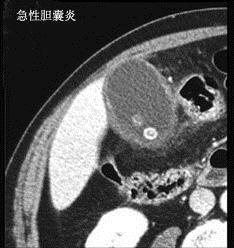

问题 有关急性胆囊炎哪项是错误 ( )

选项 A、一般无寒战 B、黄疸出现早而明显 C、右上腹可有压痛、肌紧张 D、胆囊区深吸气时有触痛反应 E、有时可扪及有触痛的肿大胆囊

答案 B